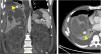

A dedicated CT scan of the liver showed new haematomas forming around the liver, and a 1.5cm pseudoaneurysm at the subdiaphragmatic surface of segment VII of the liver (Fig. 1).

A subsequent angiogram done via a right femoral approach confirmed the presence of this pseudoaneurysm which was being supplied by the superior branch of the right phrenic artery. Embolisation coils were placed in the pseudoaneurysm sac and in its feeding artery (Fig. 2).